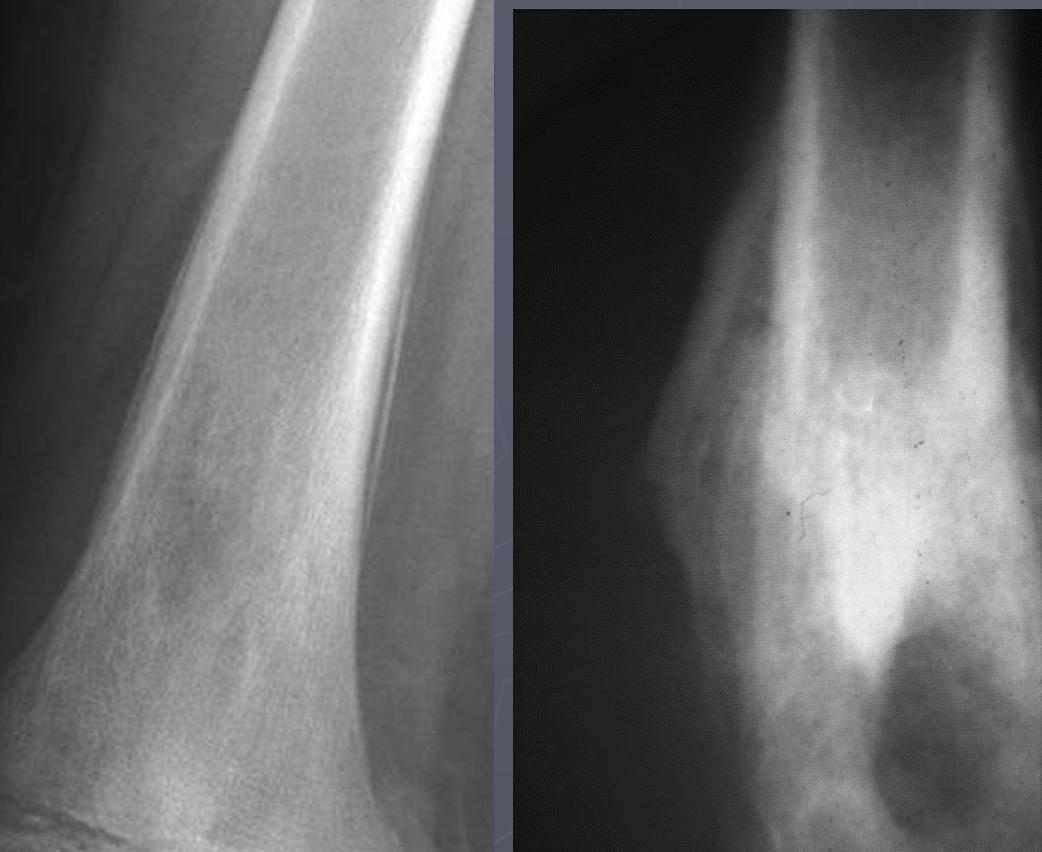

Which radiographs show an active vs. inactive pattern of periosteal reaction?

Left 2 radiographs: inactive; smooth, well defined margins

Right 2 radiographs: active; fuzzy, less sharp margins